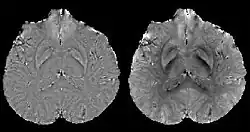

COSMOS assumes a model-free susceptibility distribution and keeps full fidelity to the measured data. This method has been validated extensively in in vitro, ex vivo and phantom experiments. Quantitative susceptibility maps obtained from in vivo human brain imaging also showed high degree of agreement with previous knowledge about brain anatomy. Three orientations are generally required for COSMOS, limiting the practicality for clinical applications. However, it may serve as a reference standard when available for calibrating other techniques.

MEDI has also been validated extensively in phantom, in vitro and ex vivo experiments. In an in vivo human brain, MEDI calculated QSM showed similar results compared to COSMOS without statistically significant difference.[15] MEDI only requires a single angle acquisition, so it is a more practical solution to QSM.

Thresholded k-space division[12][17] only requires a single angle acquisition, and benefits from the ease of implementation as well as the fast calculation speed. However, streaking artifacts are frequently present in the QSM and the susceptibility value is underestimated compared to COSMOS calculated QSM.